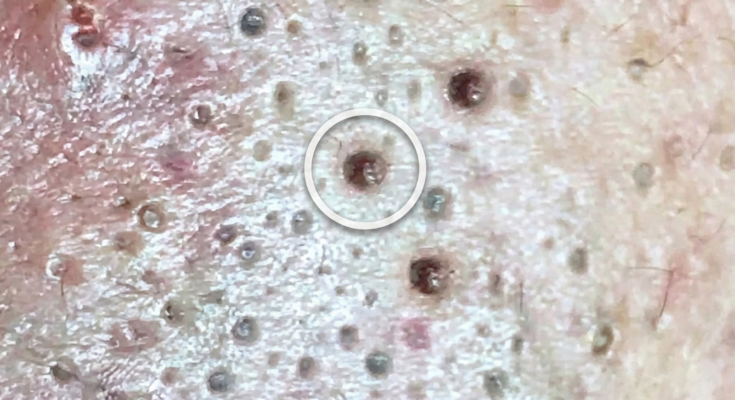

Professional chemical peels are dermatologic procedures designed to accelerate controlled exfoliation of the skin, targeting processes that contribute directly to acne formation. Acne develops when excess sebum production combines with abnormal follicular keratinization, leading to clogged pores and the formation of comedones such as blackheads and whiteheads. As keratinocytes accumulate within the follicle and mix with oil, microcomedones form beneath the surface. Chemical peels use specific acids to loosen the bonds between these surface cells, promoting more uniform shedding and helping reduce the buildup that contributes to pore blockage.

Superficial and medium-depth chemical peels commonly contain alpha hydroxy acids such as glycolic acid, beta hydroxy acids such as salicylic acid, or combination formulations tailored to acne-prone skin. Salicylic acid is particularly useful in oily skin because it is oil-soluble, allowing it to penetrate into pores and help dissolve debris within the follicle. Glycolic acid works more on the skin surface, encouraging exfoliation and improving texture. In clinical settings, higher-strength peels may be used under professional supervision to address persistent comedonal acne, post-inflammatory hyperpigmentation, and uneven skin tone associated with prior breakouts.

Professional peels may also improve the appearance of enlarged pores by reducing congestion and smoothing the surrounding skin surface. However, they do not permanently shrink pores, as pore size is largely determined by genetics and sebaceous gland activity. Results tend to be gradual and cumulative, often requiring a series of treatments spaced several weeks apart. Maintenance sessions may be recommended depending on acne severity and individual skin response.